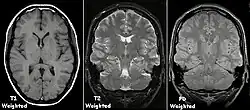

T1 and T2

Each tissue returns to its equilibrium state after excitation by the independent relaxation processes of T1 (spin-lattice; that is, magnetization in the same direction as the static magnetic field) and T2 (spin-spin; transverse to the static magnetic field). To create a T1-weighted image, magnetization is allowed to recover before measuring the MR signal by changing the repetition time (TR). This image weighting is useful for assessing the cerebral cortex, identifying fatty tissue, characterizing focal liver lesions, and in general, obtaining morphological information, as well as for post-contrast imaging. To create a T2-weighted image, magnetization is allowed to decay before measuring the MR signal by changing the echo time (TE). This image weighting is useful for detecting edema and inflammation, revealing white matter lesions, and assessing zonal anatomy in the prostate and uterus.

The standard display of MRI images is to represent fluid characteristics in black and white images, where different tissues turn out as follows: